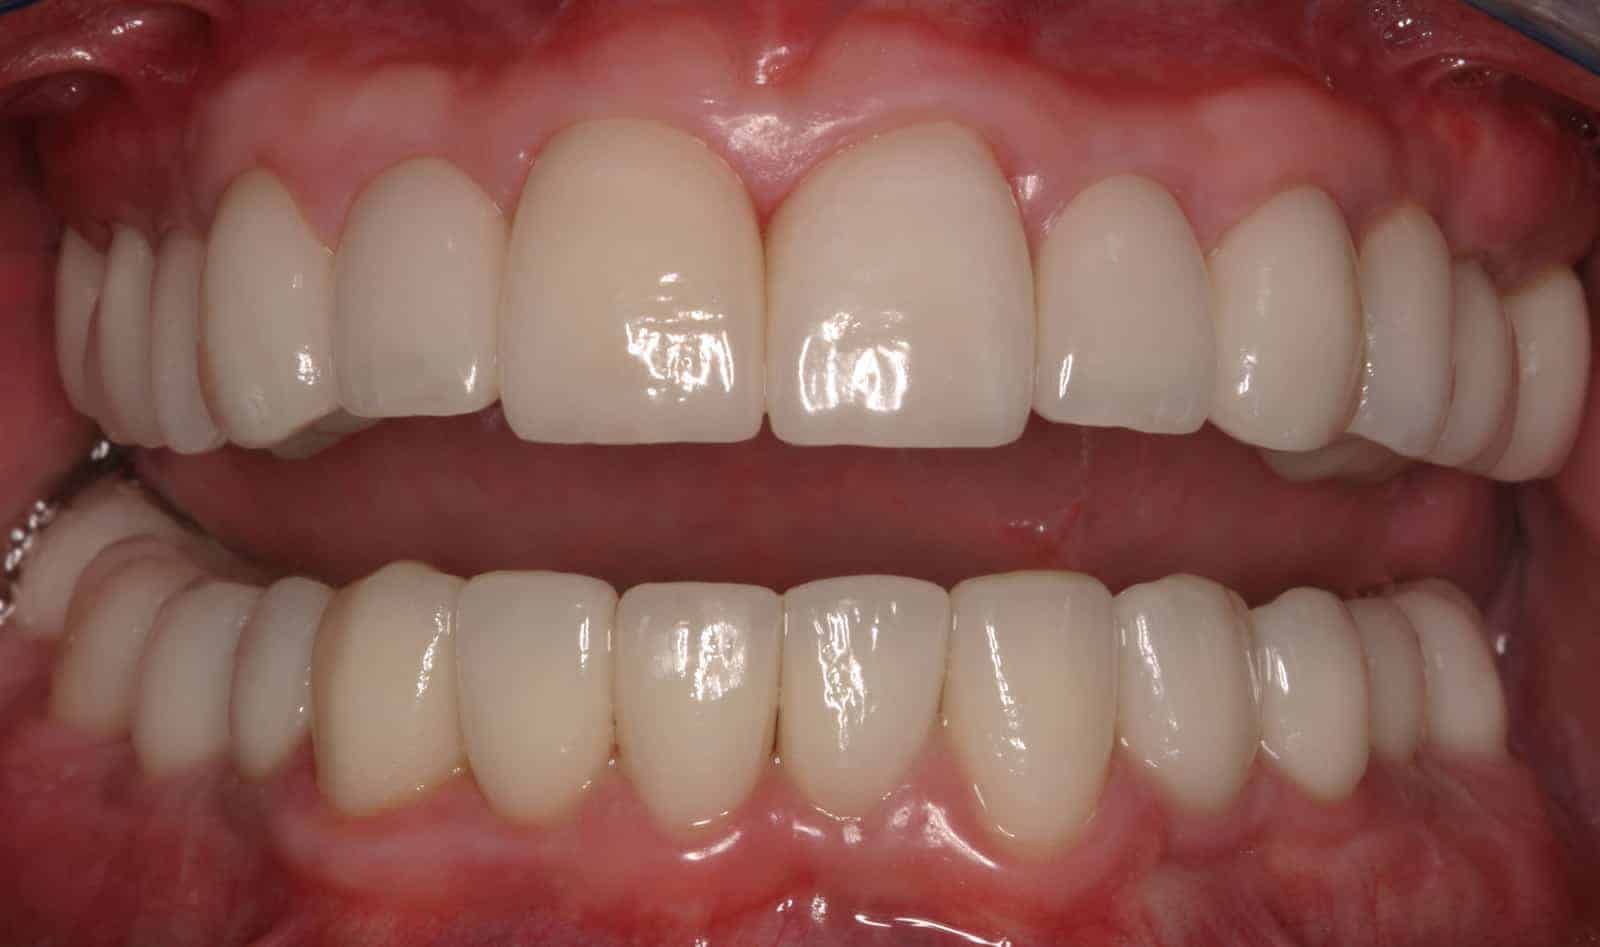

After:Â Implants were then placed by the team oral surgeon utilizing surgical guides fabricated by Dr. Leopardi. Dr. Leopardi then performed a complete dental (full mouth) rehabilitation: full coverage, conservative bonded porcelain restorations on natural teeth; all ceramic implant restorations on the upper lateral incisor implants (sited 7 and 10), porcelain fused to gold implant restorations on implants 3, 14, 19, 21, 23, 25, 28 and 29, at increased occlusal vertical dimension. Patient was restored to full function and aesthetics, significantly improving quality of life.